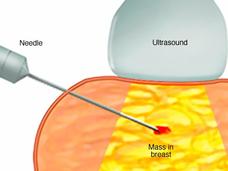

New Approach Uses Much Less Tissue to Analyze Tumor Proteins and Genes

Researchers have developed a “microscaled” approach to analyze the proteins and genetic changes (proteogenomics) of a tumor that uses tissue from a core needle biopsy. The analyses can provide important information that may help guide treatment.